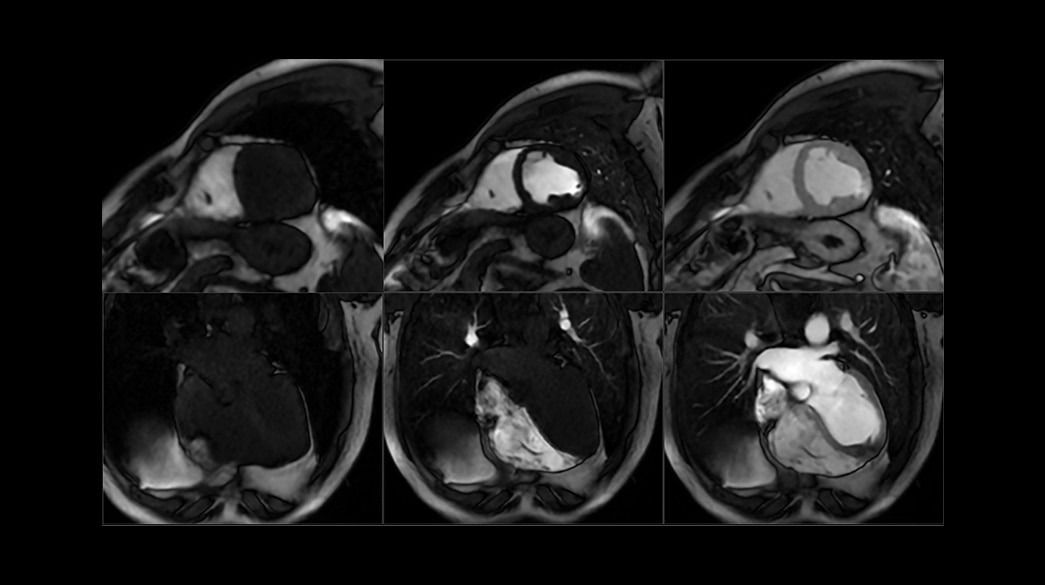

Cardiovascular MRI imaging applications

Diagnostic confidence and consistency

<p>MDE Plus – compatible with AIR Recon DL</p>

<p>FIESTA Cine</p>

<p>2D Phase Contrast</p>

<p>Fluoro Trigger MRA</p>

<p>TRICKS</p>

Precision and personalization

<p>ViosWorks</p>

<p>3D Heart – compatible with AIR Recon DL</p>